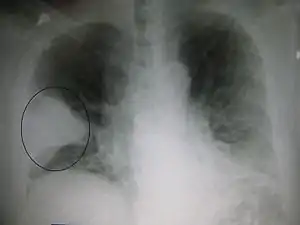

| تصویر رادیوگرافی قفسه سینه شخص مبتلا به تارا باکتریایی پیشرفته. | |

تصاویر اشعه ایکس از سینه پهلو به سینه پهلو لختهای، سینه پهلو برونشی (همچنین با عنوان سینه پهلو بخشی شناخته میشود) و سینه پهلو بینابینی قابل طبقهبندی است.[41] سینه پهلو اکتسابی باکتریایی، بهطور معمول تجمع ریوی در یک لوب سگمنتال ریه را نشان میدهد که به آن سینه پهلو لختهای میگویند.[21] با این حال ممکن است یافتهها متفاوت باشند و الگوهای دیگری در انواع دیگر سینه پهلو شایع است.[21] سینه پهلو آسپیراسیون ممکن است با تیرگی دوطرفه و عمدتاً در پایین ریهها و در سمت راست وجود داشته باشد.[21] تصاویر رادیوگرافی سینه پهلو ویروسی ممکن است طبیعی به نظر برسد، بیش از حد متورم باشد، مناطق لکهدار در هر دو طرف مشاهده شود، یا شبیه سینه پهلو باکتریایی، تجمع لختهای را نشان دهد.[21] ممکن است نتایج رادیولوژی در مراحل اولیه بیماری مشاهده نشود، بهویژه در صورتی آب بدن از دست رفته باشد؛ یا ممکن است تفسیر آن در کسانی که چاق هستند یا سابقه بیماری ریوی دارند، دشوار باشد.[12] سیتی اسکن میتواند اطلاعات بیشتری را در موارد نامشخص در اختیار قرار دهد.[21]